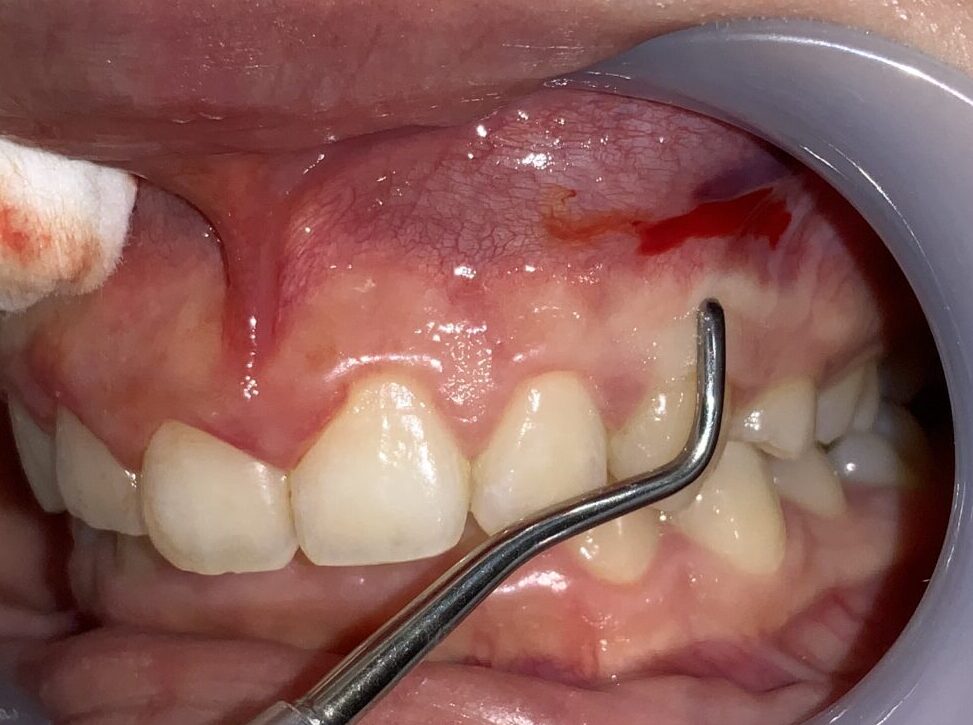

最後に犬歯の検査をします。

犬歯もこのように小さな形ではなく、綺麗な形になります。

八重歯にならないように細心の注意をします。